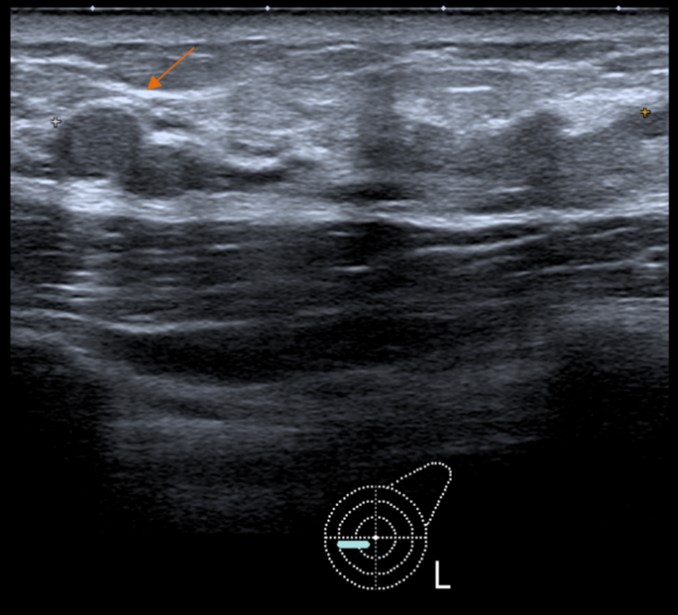

Second-look ultrasound (Fig. 3) showed this additional lesion as a round, apparently solid nodule, with slight posterior acoustic enhancement. Core needle biopsy also revealed MEC.

Figure 3: Second-look ultrasound depicting the additional lesion as a round nodule - core needle biopsy also revealed MEC of the breast.